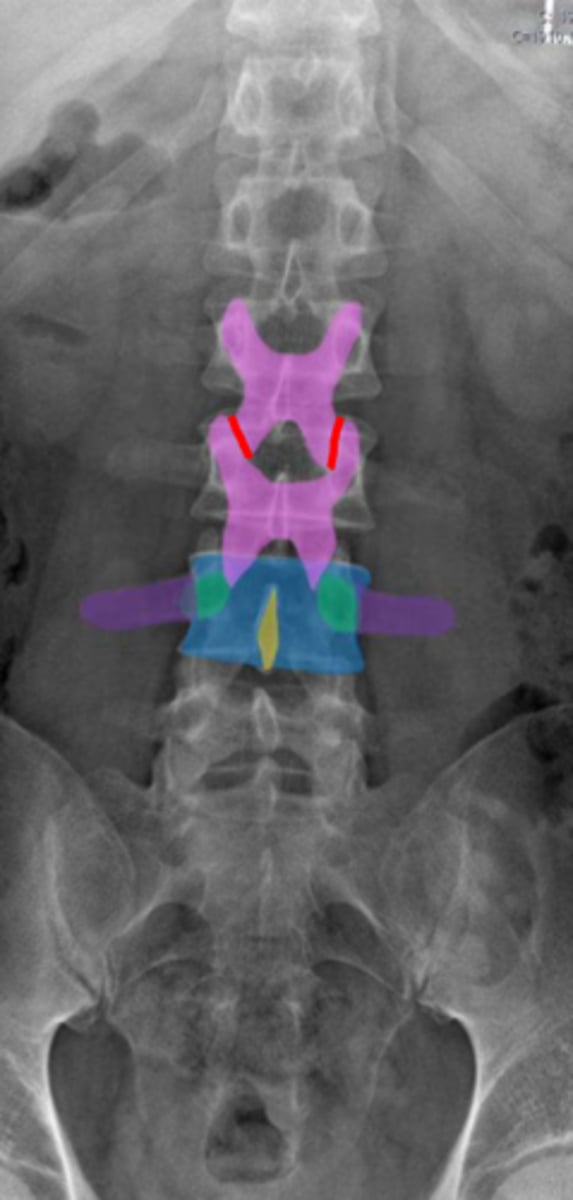

lumbar

What vertebrae is being examined?

lumbar vertebral body

Identify the blue structure

pedicles

Identify the green structure

transverse processes

Identify the purple structure

spinous processes

Identify the yellow structure

joint space between superior and inferior articulating facets

Identify the red line

intervertebral foramen

Identify the orange structure